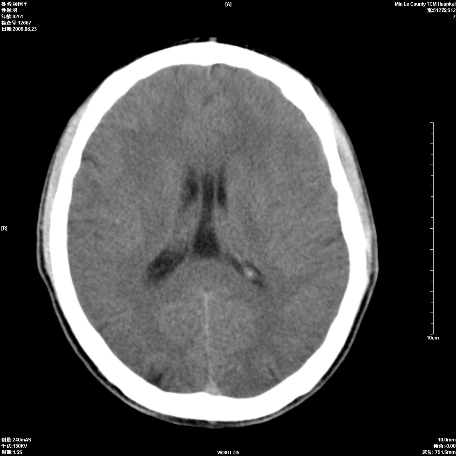

以下是引用zxl51642在2009-6-23 14:15:00的发言:[br]1、颅内未见血肿,颅骨未见骨折;[br]2、双侧苍白球对称性钙化,透明隔间腔及verga氏腔形成。